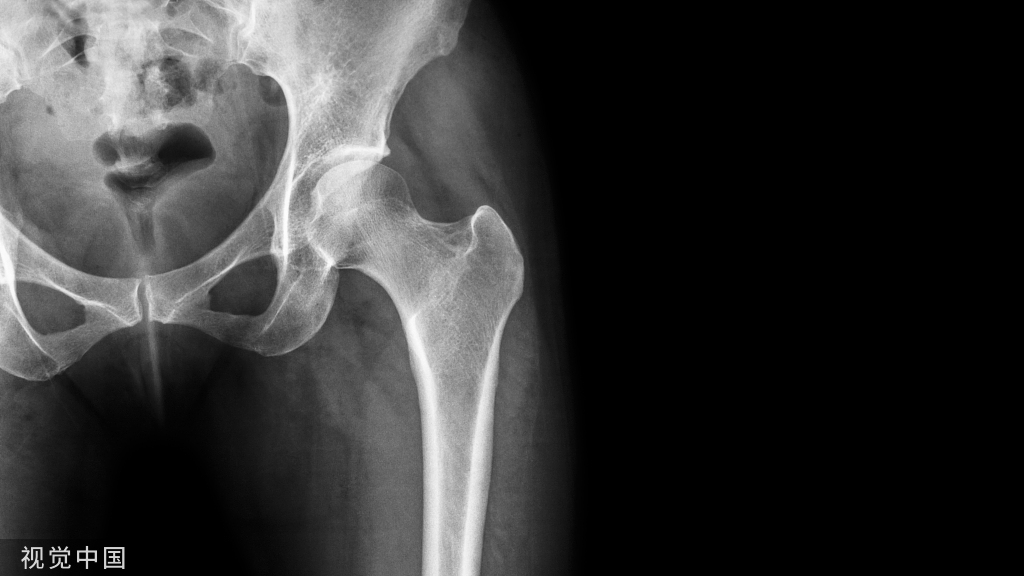

03、政策利好,国产骨科手术机器人大量涌现

随着骨关节患者数量的上涨,对骨科手术机器人等医疗器械的需求随之上涨。全球骨科手术机器人市场规模在未来5年内呈持续上涨趋势,2020年全球骨科手术机器人市场规模达到13.9亿美元,预计在2023年底,全球骨科手术机器人市场可以达到25.5亿美元。

骨科手术机器人,主要应用于脊柱外科、关节外科、创伤骨科。骨科手术机器人产业链结构中,上游为零部件供应商,主要为控制系统、定位导航系统、机械臂装置等;产业链中游为骨科手术机器人制造商,产业链下游为应用领域,主要为骨科医院,医疗机构等。国外龙头企业如捷迈邦美、施乐辉、强生、史赛克等骨科手术机器人产品均有革新。

国内由于骨科机器人单价高且未纳入医保覆盖范围,引入医院主要以三甲医院和少量私立医院为主,其中三甲医院占比最重,占比为70%。我国骨科机器人的发展仍处于市场导入阶段,医生接受度和市场渗透率有很大提高空间。

国家多项政策助力,骨科手术机器人有望进一步普及。近年来多项利好骨科手术机器人的政策出台,医用机器人等高性能诊疗设备被列入重点支持方向。随着越来越多新产品获批上市,以及昂贵费用逐步纳入医保,骨科手术机器人有望在全国加快普及。目前,中国已经获批注册证的骨科机器人厂商有:骨科-关节手术机器人:微创畅行、和华瑞博、键嘉、骨圣元化、壹点灵动(爱康医疗旗下);骨科-脊椎手术机器人:天智航、鑫君特、铸正、佗道、普爱医疗、美亚光电;骨科-关节手术机器人:柳叶刀;骨科-创伤手术机器人:罗森博特。

骨盆骨折闭合复位、微创治疗对医生的经验与技术要求较高,是骨科中难度较大的手术之一。骨盆复位手术中,医生和患者对机器人的辅助有着强烈的“刚需”。骨盆骨折复位机器人的细分赛道在全球范围内都少有玩家入局,罗森博特选择切入骨盆复位机器人细分赛道,避开激烈竞争的同时布局国际市场,通过高难度的术式切入,实现真正意义上的“弯道超车”,即“挑战全球范围内公认的难题,做真正创新的事情”。